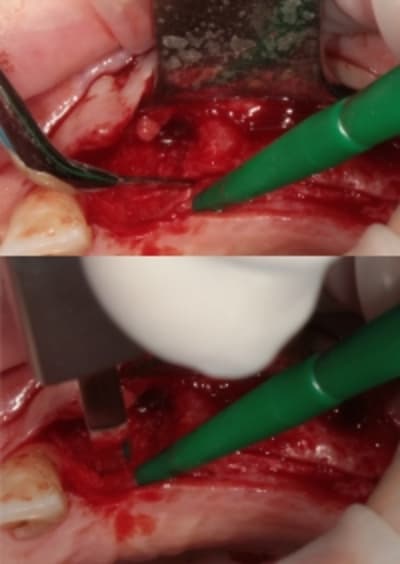

3:

de nouveau ostéotome "lame" angulé

Ostéotome droit, plus étroit que le premier.

4:

évolution

Tatum D1

5:

évolution il faut obtenir de quoi placer un diamètre 3,4

de nouveau lame 15 pour incision de décharge verticale

6

lame 15

manuel et impacté au maillet (cool)